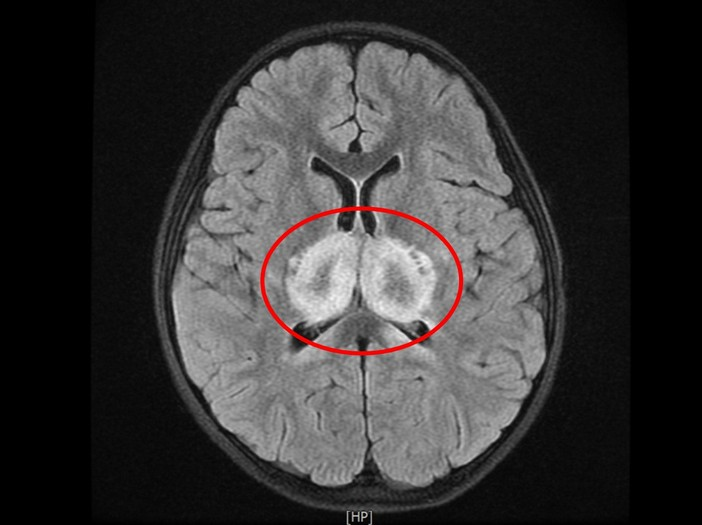

▲蔡小妹核磁共振掃描影像顯示視丘區域發白,即此區塊正嚴重發炎。

「解決危急病況只是第一步,後續還有一道道難關要解決,這是個漫長的過程。」花蓮慈院兒科病房主任陳明群表示,蔡小妹剛送至醫院急診時呈現無法說話、嗜睡、癲癇發作、抽筋、血壓下降、心跳偏低卻會時而飆升的狀態,生命徵象非常不穩定,核磁共振掃描影像顯示「視丘」區域發白,即此區塊正嚴重發炎。陳明群醫師指出,視丘是大腦的中繼站和樞紐,無論是感覺神經要將訊息傳回大腦,或運動神經要把指令從大腦傳出,都必須經過視丘轉換神經元傳遞訊號;因此若視丘有嚴重細胞損傷,將會大大影響患者生命健康。

▲花蓮慈院兒科病房主任陳明群指出,視丘是大腦的中繼站和樞紐,若此處有嚴重細胞損傷,將可能會嚴重影響患者生命健康。